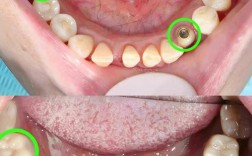

(图片来源网络,侵删)- 这指最终修复的牙冠数量是 3颗,这3颗牙冠通过一个连接体(桥体)固定在一起,形成一个“种植桥”。

用户希望看到这种“2颗种植体支撑3颗牙冠”修复方式的示意图、实物模型图、X光片或案例照片。